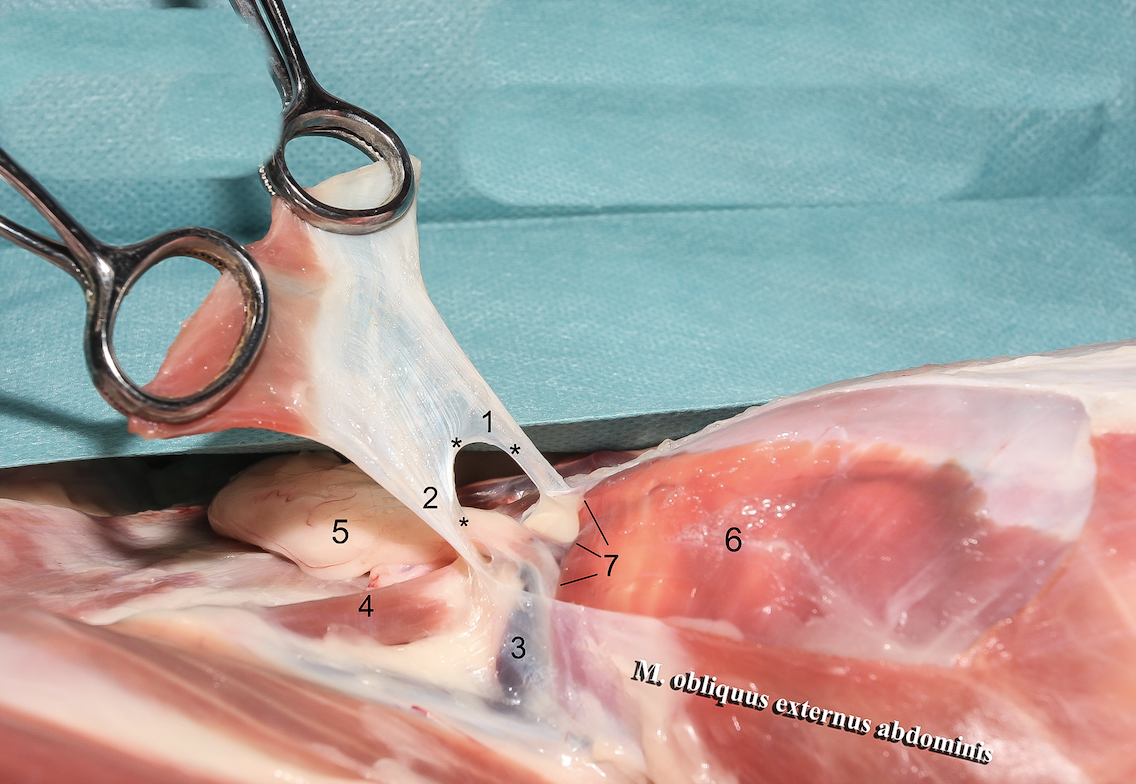

1

A

Crus mediale

6

Q

2

A

Crus laterale

7

Q

3

A

A./v. pudenda externa

8

Q

4

A

A./v. femoralis

9

Q

5

A

Processus vaginalis

10

Q

6

A

A./v. pudenda externa